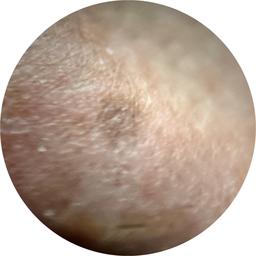

ISIC_5202282

IP_6423627

IL_0565396

anatom_site_1 Upper extremity

anatom_site_general upper extremity

fitzpatrick_skin_type I

image_type dermoscopic